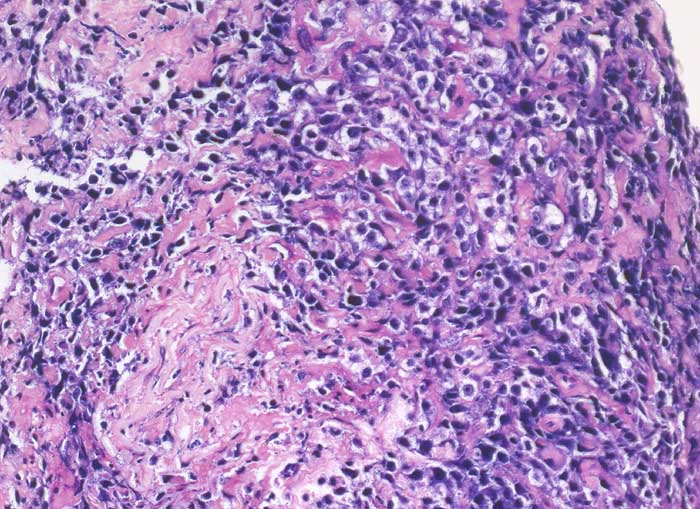

pit/ Diffuses grosszelliges B-Zell Lymphom

Diffuses grosszelliges B-Zell Lymphom

Diffuse grosszellige B-Zell Lymphome treten nicht selten in extranodalen Lokalisationen auf und können klinisch als Karzinom fehlgedeutet werden. Bei ungewöhnlicher Zytomorphologie eines malignen Tumors sollte deshalb immer auch an die Möglichkeit eines nicht epithelialen Tumors gedacht und der Befund mittels Immunzytochemie weiter abgeklärt werden. Zur Unterscheidung eines Lymphoms von einem epithelialen Tumor eignen sich der panleukozytäre Marker CD45 (LCA) und ein Panzytokeratinmarker oder BerEP4.

Beim ersten Fall handelt es sich um ein primär extranodales Lymphom des Nierenbeckens, das im Urin diagnostiziert wurde. Beim zweiten Fall handelt es sich um ein primär extranodales Lymphom im Bereich der Nebenniere mit Nachweis von Lymphomzellen im Aszites.